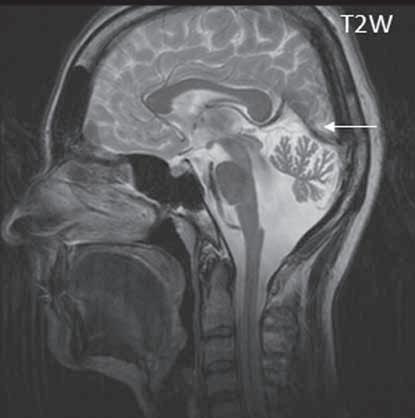

I.1.7 Chiariho malformace (ArnoldovaChiariho malformace)

Rozlišujeme tři formy (typy) této malformace. Chiari I je charakterizován sestoupením mozečkových tonzil do foramen okcipitale magnum do oblasti krční páteře (u dospělých jsou tonzily mozečku max. 5 mm pod úrovní baze lební, u malých dětí (do 10 roků) do 6 mm. Tonzily bývají na podélném řezu přirovnávány ke klínům, které jako by byly zatlučeny do týlního otvoru „pek like“. Chiari II malformace je ve 100 % doprovázena otevřeným spinálním dysrafismem (obvykle myelomeningokélou). Chiari III lze definovat jako Chiari II + okcipitální nebo cervikální encefalomeningokéla. Chiari IV, kde je navíc přítomna hypoplazie mozečku, do této skupiny nezařazujeme, vývojově patří do poruch ventrální indukce.

Zobrazení

Chiari I: CT a MR zobrazí malou zadní jámu lební, absenci cisteren zadní jámy lební, pokles tonzil, krátký a konkávní klivus, poruchu cirkulace mozkomíšního moku v oblasti foramen magnum a následný hydrocefalus. MR navíc může prokázat edém krční míchy a ve vysokém procentu případů hydrosyringomyelii.

Chiari II: CT a MR zobrazí malou zadní jámu lební, absenci nebo výraznou redukci cisterny cerebelomedulární a dalších kmenových cisteren, konkávní klivus. Mohou být abnormality v oblasti foramen okcipitale magnum, nízký úpon tentoria, někdy absence nebo fenestrace falx cerebri. MR lépe ukáže kaudálně uloženou a protáhlou IV. komoru (někdy je přirovnávána až ke stéblu slámy), protažený pons a další možné, přidružené abnormality (hydrosyringomyelii, agenezi, hypogenezi nebo fenestraci corpus callosum…).

Obr. I.1.7a Sestup mozečkových tonzil (šipka), Chiariho malformace I

Obr. I.1.7b Sestup mozečkových tonzil, „pek like“ (šipka), Chiariho malformace I c d